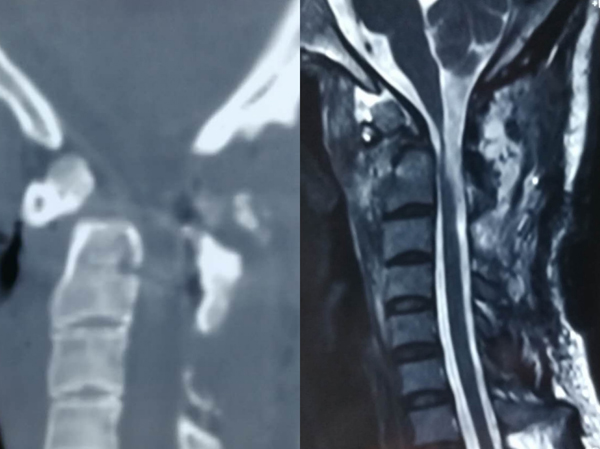

术前CT及磁共振

术后CT及磁共振